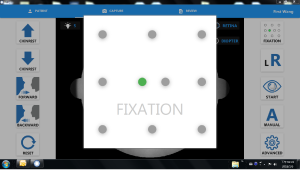

10 мішеней для фіксації

Можна обрати десять цілей внутрішньої фіксації. Диск, ямка, макула або інші периферійні ділянки сітківки можуть бути захоплені, вибравши вказану фіксацію.

| Фіксація | Внутрішня | 10 точок |